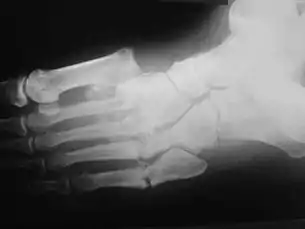

A apresentação clínica varia dependendo do estágio da doença, começa com um edema leve e evolui a um inchaço e deformidade cada vez maiores. Inflamação, eritema, dor e aumento da temperatura da pele (3-7 graus Celsius) ao redor da articulação podem ser perceptíveis ao exame físico. Raios-X podem revelar reabsorção óssea e alterações degenerativas na articulação. Esses achados na presença de pele íntegra e perda de sensibilidade tátil protetora servem para diagnósticos da artropatia de Charcot aguda.